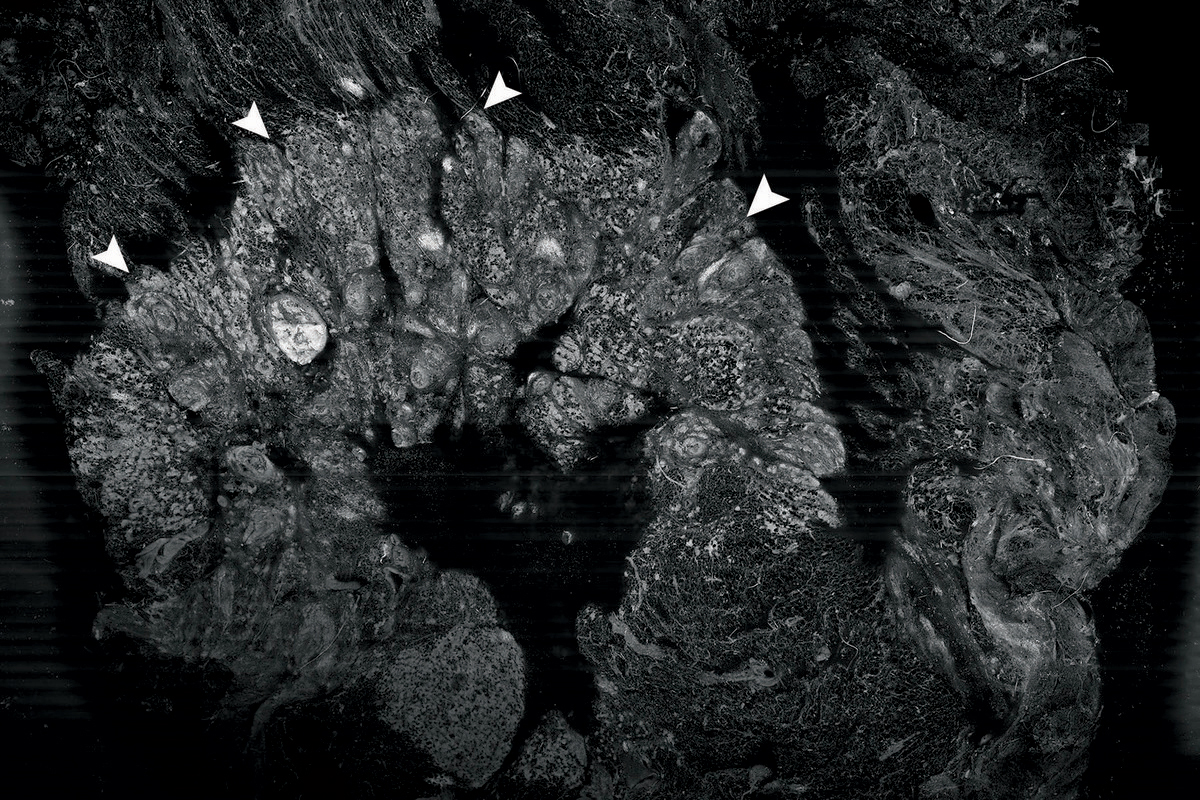

A cross section of a piece of breast tumor tissue imaged by confocal mosaicking microscopy, a method Memorial Sloan Kettering researchers are developing to make pathology in the OR more effective.